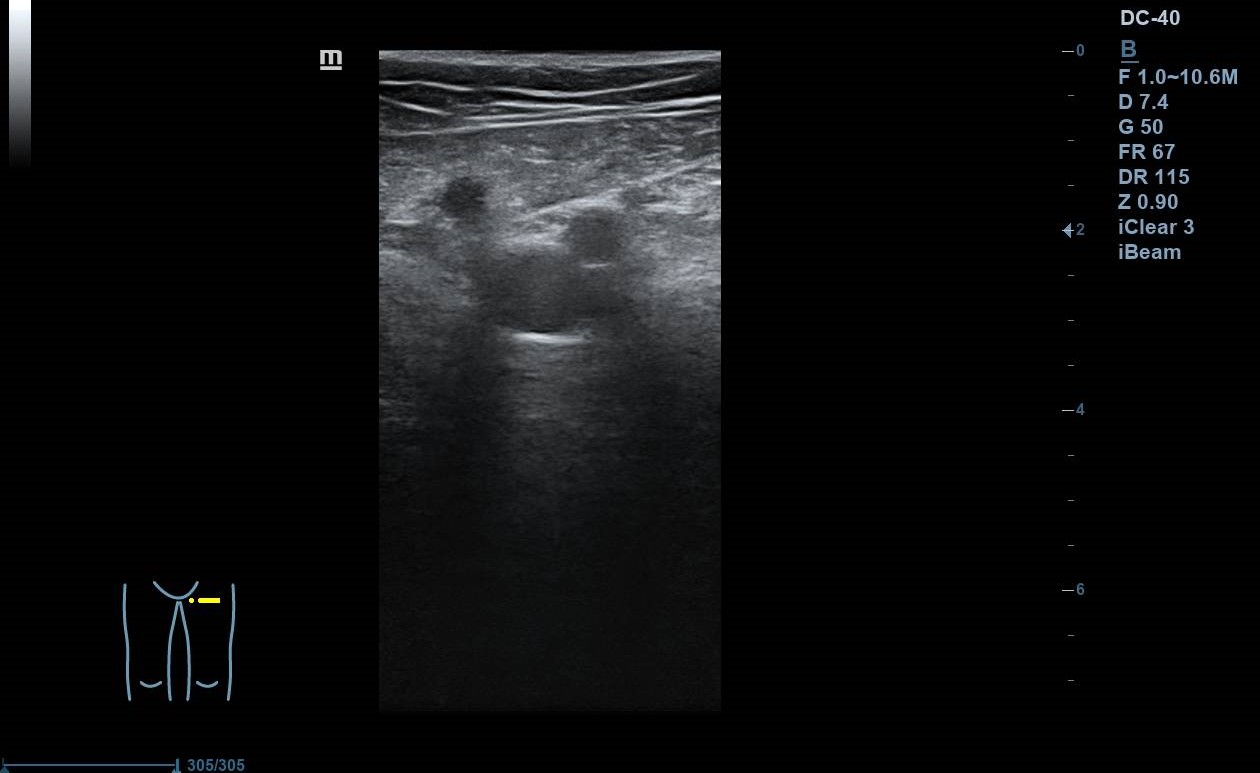

Se realiza ecografía Doppler en el Centro de Salud: se exploran con sonda lineal ambos MMII a nivel inguinal y poplíteo, constatando colapsabilidad, presencia de flujo y ausencia de material ecogénico a nivel de vena femoral común y poplítea. Colocando sonda en el punto doloroso observamos vena safena interna no colapsable. Nos desplazamos superiormente, siguiéndola hasta la unión safenofemoral, sin observar colapsabilidad durante el trayecto.

Juicio clínico: TVS en vena safena interna de al menos 5 cm con afectación próxima a cayado.

Un mes después se repite ecografía en el centro de salud observándose mejoría de la TVS.